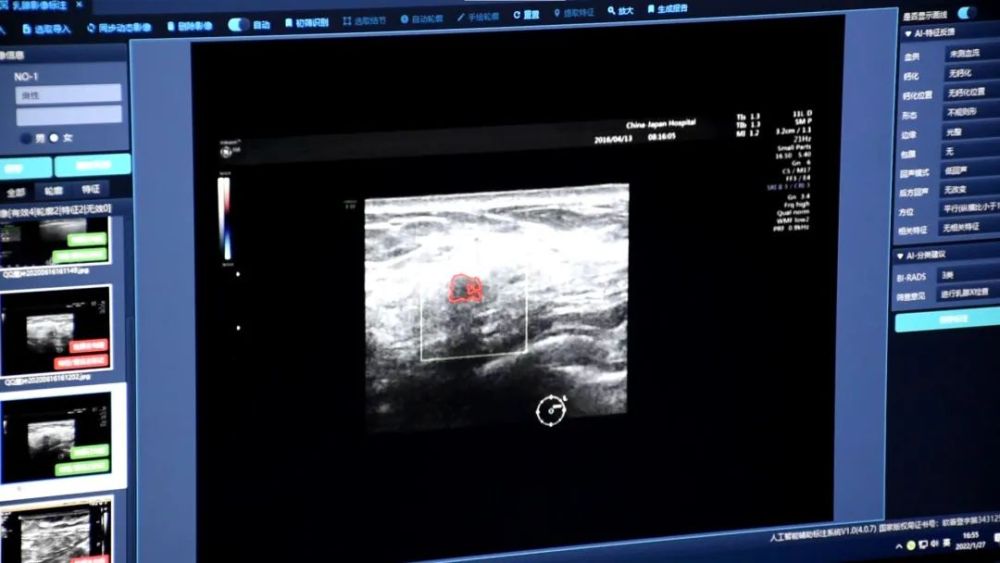

为便于走基层小分队进一步理解当前研究,博士生韩霖演示了该实验室开发的“超云-医学超声乳腺癌智能辅诊软件”。该软件运行只需一个“命令”,一个被红线标注出的乳腺肿瘤就清晰地呈现在屏幕中央,旁边的参数根据乳腺超声检查指南的要求显示出了该肿瘤的血供、钙化、边界、回声等情况,以及BI-RADS分级和良恶性,这些信息可以为影像诊断提供极大帮助,该软件目前已在一些基层医院进行测试试用。

超声乳腺癌智能辅诊软件界面